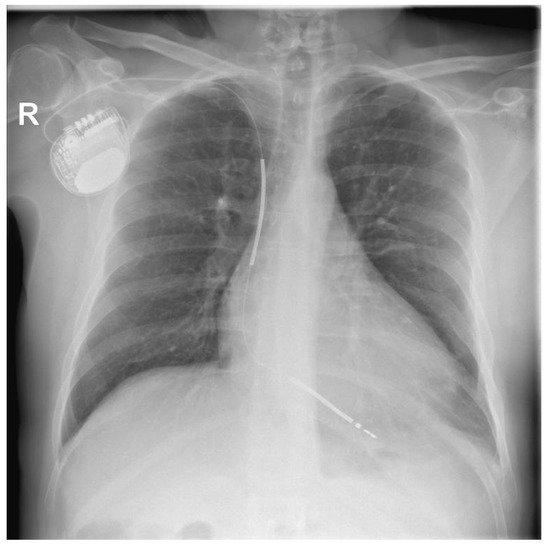

At the time of admission to our department, the patient was asymptomatic. The ECG showed a sinus rhythm with left bundle-branch block. A chest X-ray revealed an increased cardiothoracic ratio, a pulse-generator ICD placed subcutaneously in the left subclavian area, and two dual-coil defibrillation leads in the apex of the right ventricle (Figure 2).

Figure 2. Chest X-ray at the time of admission at the hospital.